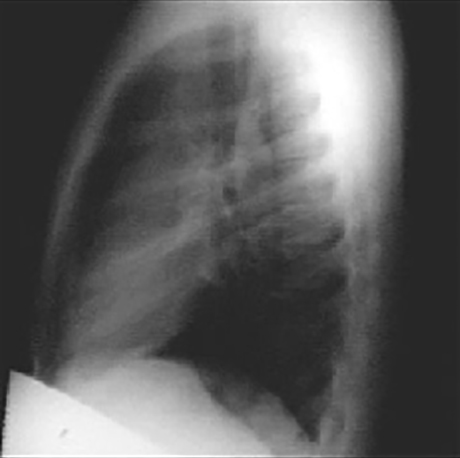

Dilated Ascending Aorta (PA and lateral)

These chest X rays show a dilated ascending aorta.

The PA view demonstrates dilatation of the ascending portion of the aorta as evidenced by a prominent bulge in the right mediastinal shadow. Note that the heart size is normal, as reflected by a cardiothoracic ratio less than 50%. The lateral view shows a dilated ascending aorta as evidenced by the shadow anterosuperior to the heart.